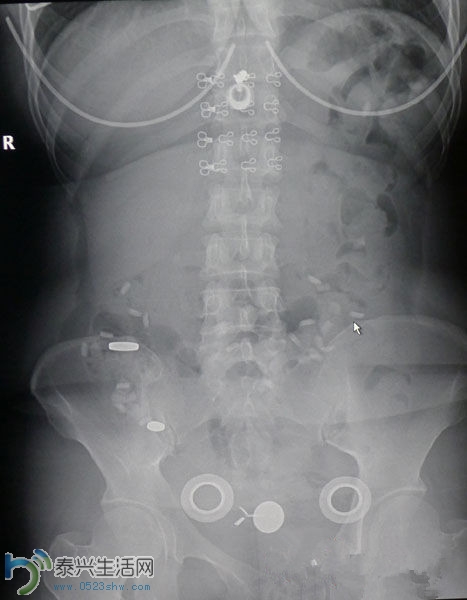

杨女士的DR片显示腹部有异物

随后,记者来到保亭人民医院,通过医生调取放射科资料,5月31日下午4点11分,杨女士的确使用过“陈盛翔”的假名做过DR检测,医生能在DR片上清楚判断出腹中确有异物。诊断结果和影响表现为:腹部异物,腹部见大小不等圆形及环形金属密度影及多个不规则形高密度影。